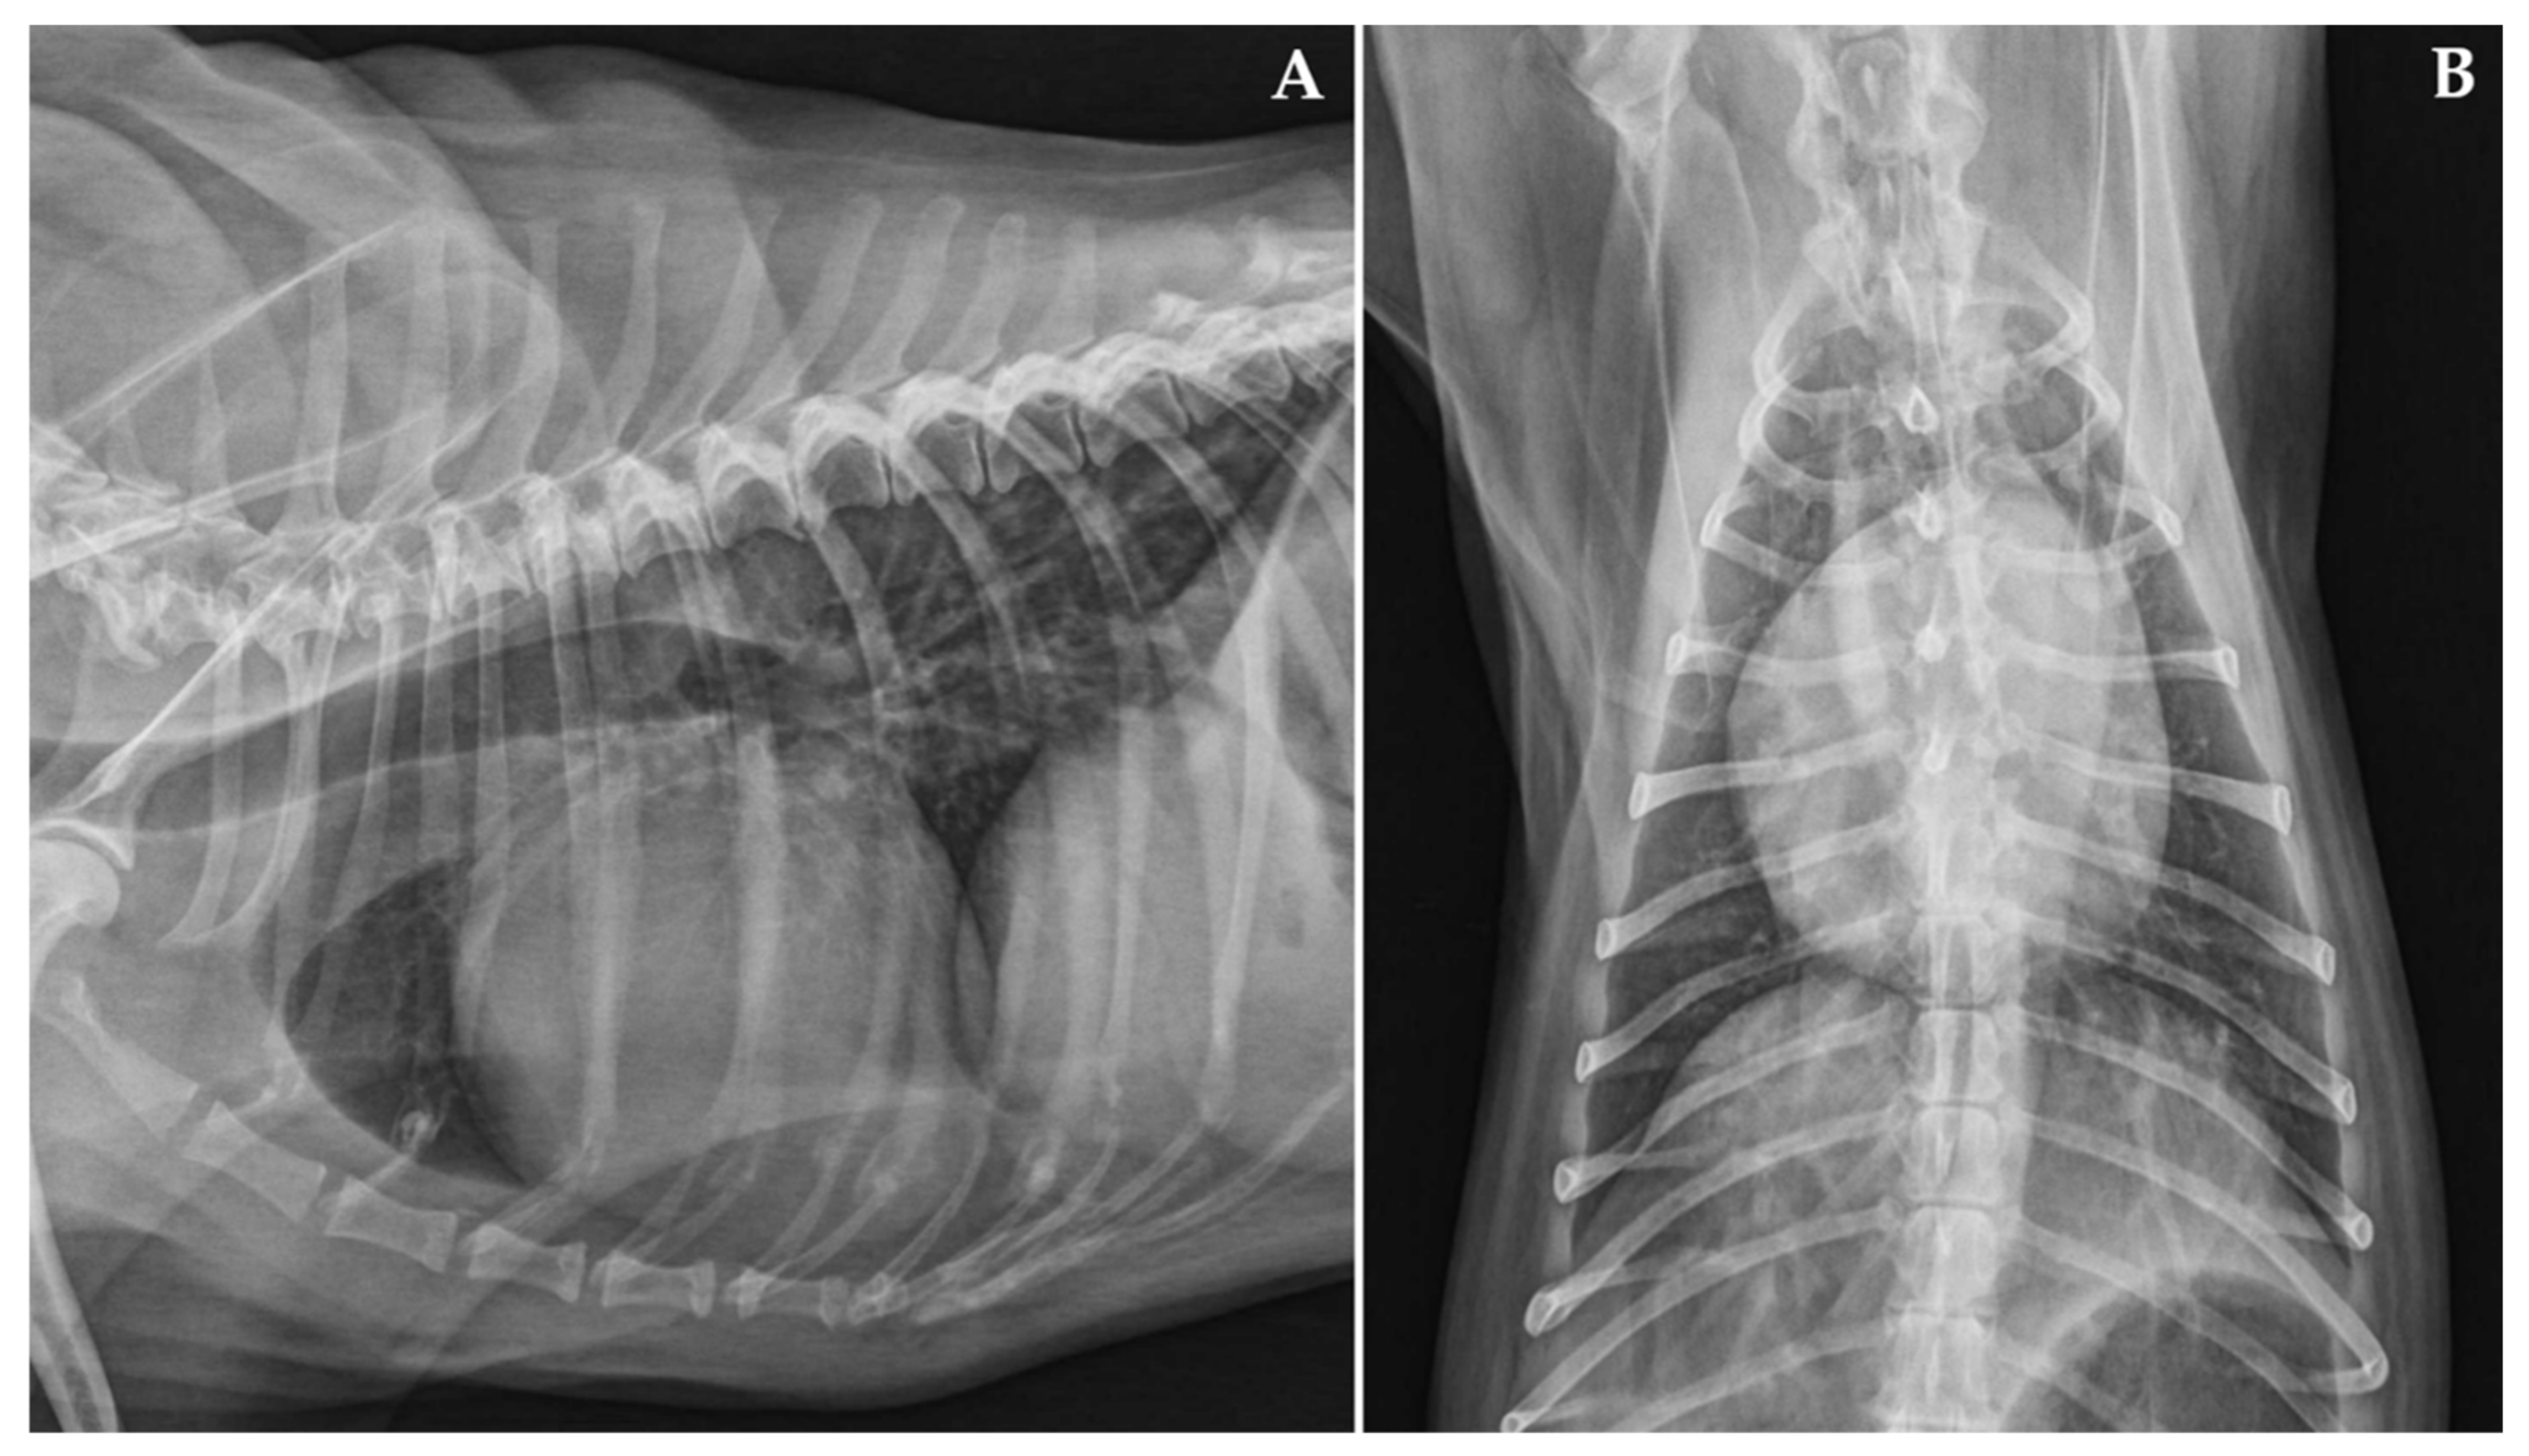

2. Materials, Methods and Results

Case Description and Clinical Investigations